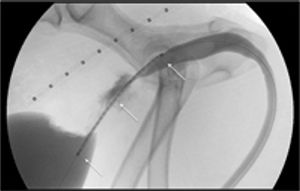

Urethral stenting for patients with malignant obstructionByAllyson Berent, DVM, DACVIMAugust 1st 2011This effective, minimally invasive outpatient procedure can offer immediate relief of stranguria.